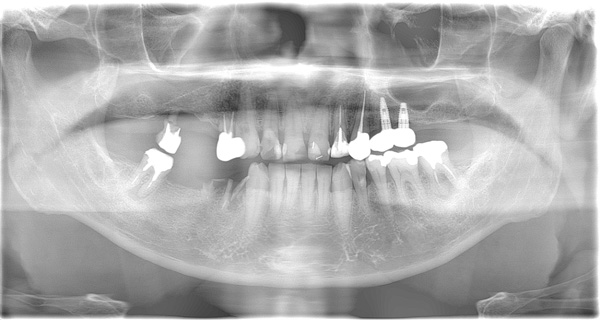

BEFORE

| 年代・性別 | 50代 女性 |

|---|---|

| 主訴 | 左上のブリッジがグラグラして外れそう |

| 治療期間 | 約18ヶ月 |

| 費用 | 1,600,000円 |

| 治療内容 | インプラント、骨造成、サイナスリフト、セラミック修復 |

| 治療に伴うリスク | インプラント周囲炎 セラミックの破折、脱離 |